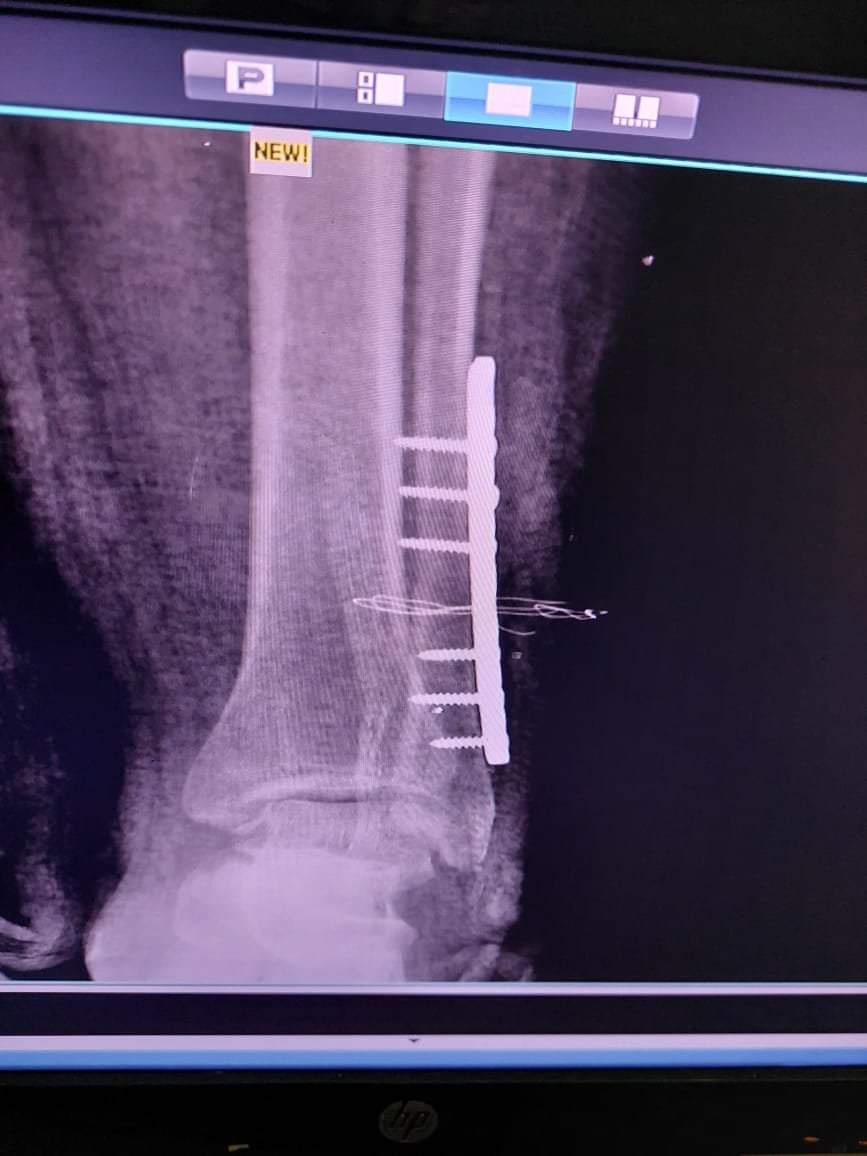

كما نجح قسم العظام في مستشفي النوبارية في اجراء عملية تثبيت كسر لعظام الكاحل الحالتين بشرائح و مسامير بقيادة د مصطفى درويش استشارى د.عادل نمير اخصائي العظام